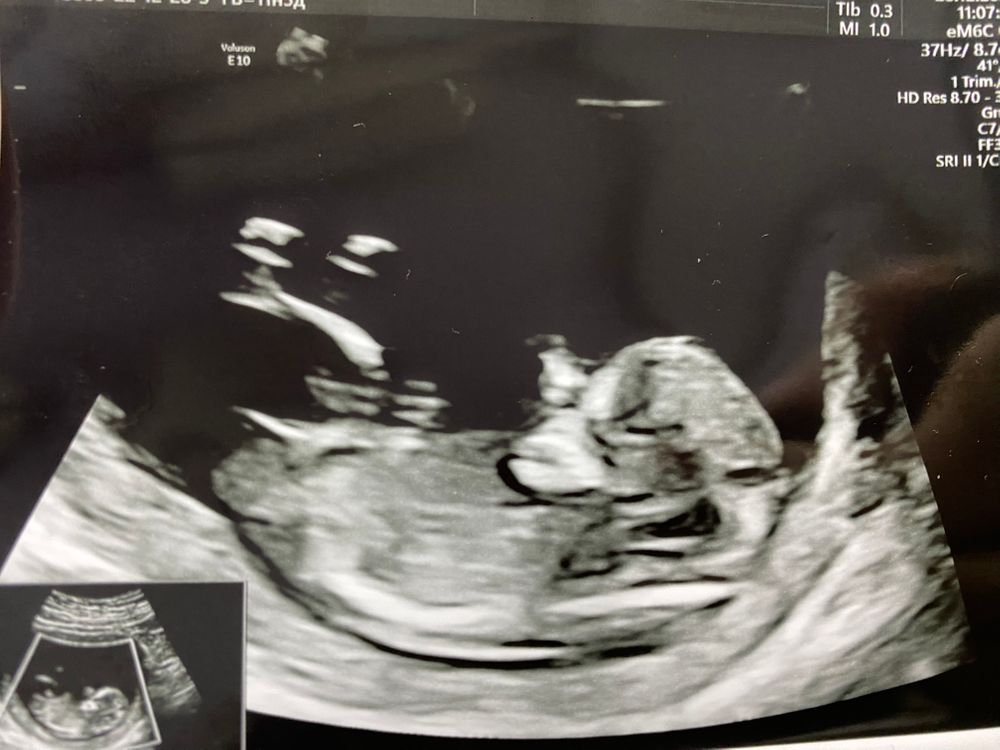

Скрининг 1

Мне кажется, девуля у вас) На первом кадре видно.

Nysha, я когда пришла, видно волновалась и он такие пируэты выдавал, не сфоткать, а когда я успокоилась - уснул, да еще и рукой лицо закрыл, понятно что фотка неудачная будет) врач даже просила встать походить, еще раз посмотрели, а он все равно вот как застыл в таком положении 😁

Похоже на девочку, но это не точно.